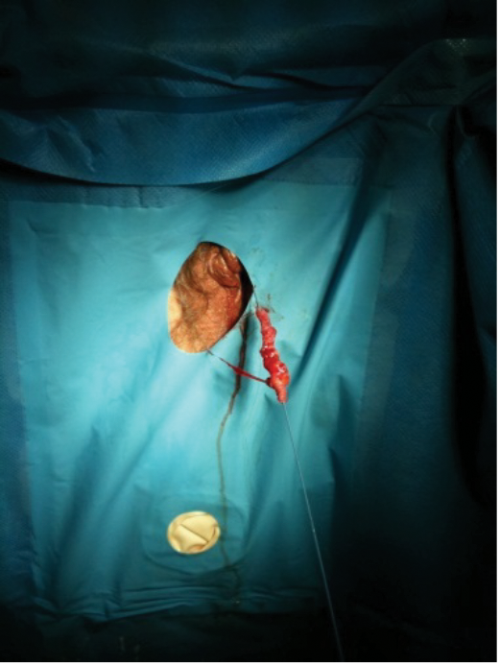

Retrograde pyelo-ureterography and subsequent ureteroscopy confirmed the diagnosis of benign PUJ obstruction. However, on withdrawing the ureteroscope under vision, the upper ureter appeared thin and possibly perforated and much to the horror of the operating surgeon the entire length followed the scope on the guide-wire (Figure 3).

Figure 3: The entire ureter on the guide-wire following withdrawal of the ureteroscope.

The opinion of a second surgeon was sought and the options of nephrostomy, auto transplantation and ileo-conduit interposition considered. However, having considered the relatively poor functioning kidney and having discussed the case with the patient’s daughter, an uneventful laparoscopic nephrectomy was performed.

Histologically there was chronic interstitial parenchymal inflammation. There was no evidence of malignancy in the ureter which revealed changes suggestive of PUJ obstruction.